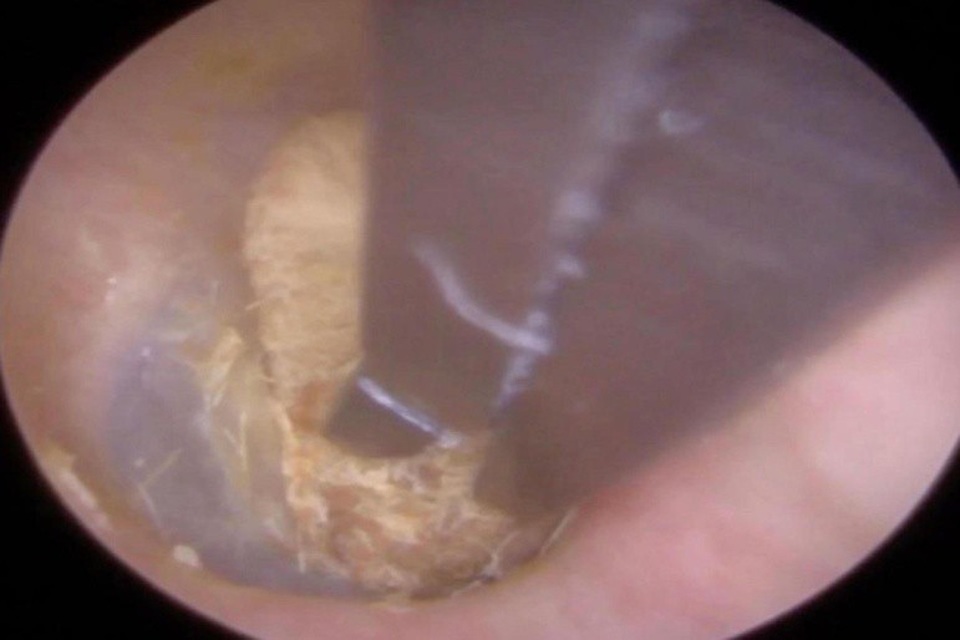

Bệnh nhân nói với bác sĩ tại phòng khám tai rằng từng có một cục bông mắc kẹt trong tai mình 2 năm về trước nhưng anh tin rằng nó đã tự rơi ra không lâu sau đó. Tuy nhiên ngược lại hoàn toàn với điều anh tin tưởng, cục bông vẫn còn ở bên trong và bị ngâm nước trong thời gian bệnh nhân đi bơi gần đây khiến tai anh sưng lên đầy đau đớn.

“Bệnh nhân phàn nàn rằng tai phải giống như bị bóp nghẹt. May mắn là màng nhĩ vẫn còn khỏe mạnh và nguyên vẹn. Mất khoảng 1 phút để loại bỏ cục bông ra khỏi tai. Đó là một công đoạn đầy tinh tế vì cục bông có thể chui vào sâu hơn, làm tổn thương màng nhĩ. Tôi phải đảm bảo rằng mình không tạo ra bất cứ lực nào vì bệnh nhân có thể thủng màng nhĩ nếu tôi làm vậy”, bác sĩ Neel Raithatha chia sẻ.